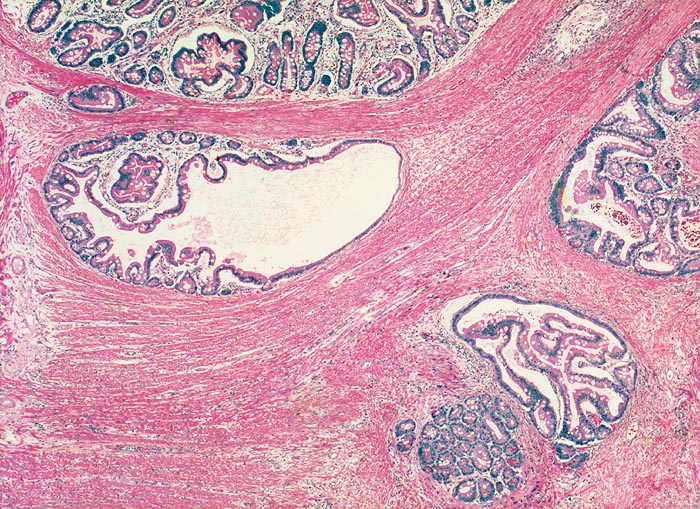

Peutz Jegher Polyp mit Pseudoinvasion

Jejunum

Benigne, in die Muscularis propria verlagerte Drüsenschläuche an der Polypenbasis imitieren ein invasives Karzinom. Die fehlenden Epithelatypien und der normale Epithelaufbau mit begleitender Lamina propria ermöglichen die Unterscheidung von einem Karzinom.

Breitbasiger Polyp von 3cm Durchmesser.

Epithelverlagerungen in die Submukosa und Muscularis propria kommen nur in Dünndarmpolypen vor.